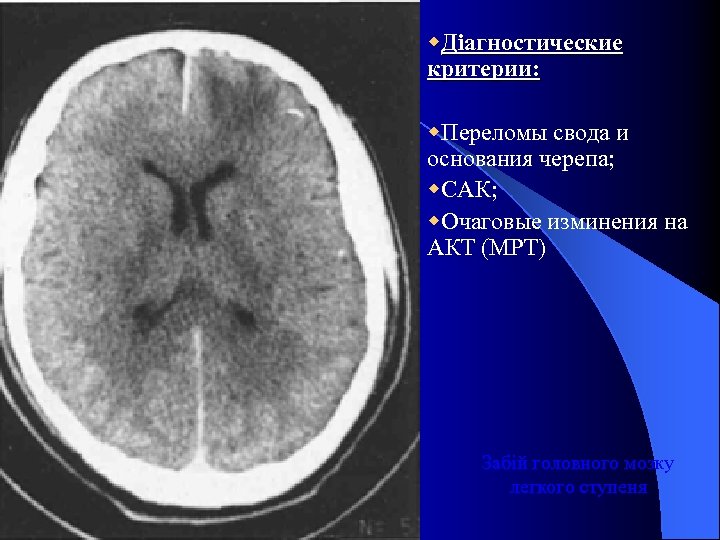

l Ушыб головного мозга легкой степени l У 10 -15% больных с ЧМТ l 14 – 15 б по ШКГ l Клиника: Потеря сознания 30 мин. – 1 час. Амнезия до 1 часа. l Общемозговие и менингеальние симптомы l Легкая очаговая симптоматика (анизокория, понижение роговичных рефлексов, слабость конвергенции, повишение или снижение сухожыльных рефлексов, с-м Маринеску – Радовичи) l Отсутствие стволових симптомов. l l Лечение: Длительность (8 – 14 сут. ) l Анальгетики, седация, ноотропы; l Дегидратация по показаниям. l

w. Діагностические критерии: w. Переломы свода и основания черепа; w. САК; w. Очаговые изминения на АКТ (МРТ) Забій головного мозку легкого ступеня